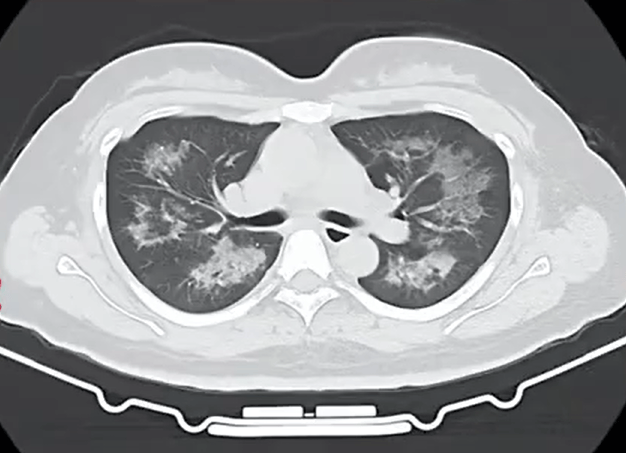

胸部CT进一步显示,她的双肺出现多发斑片状模糊影,被诊断为间质性肺炎虚拟货币投资。医生判断,病因很可能与她近期长期接触的某类物质相关。经过医生反复细致地询问病史,小江才说出自己存在长期、频繁使用定妆喷雾的情况。